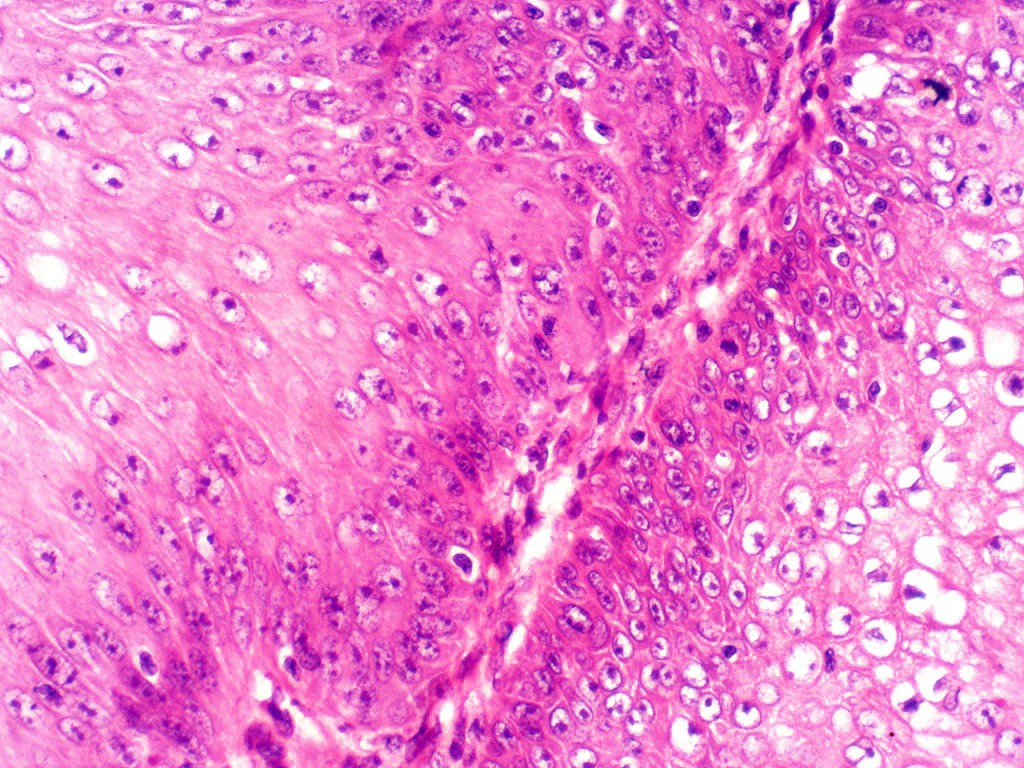

•Well differentiated epithelium characteristically having a ground glass appearance

•Marked tumor necrosis

•Intraepithelial abscesses

•Basally located mitoses